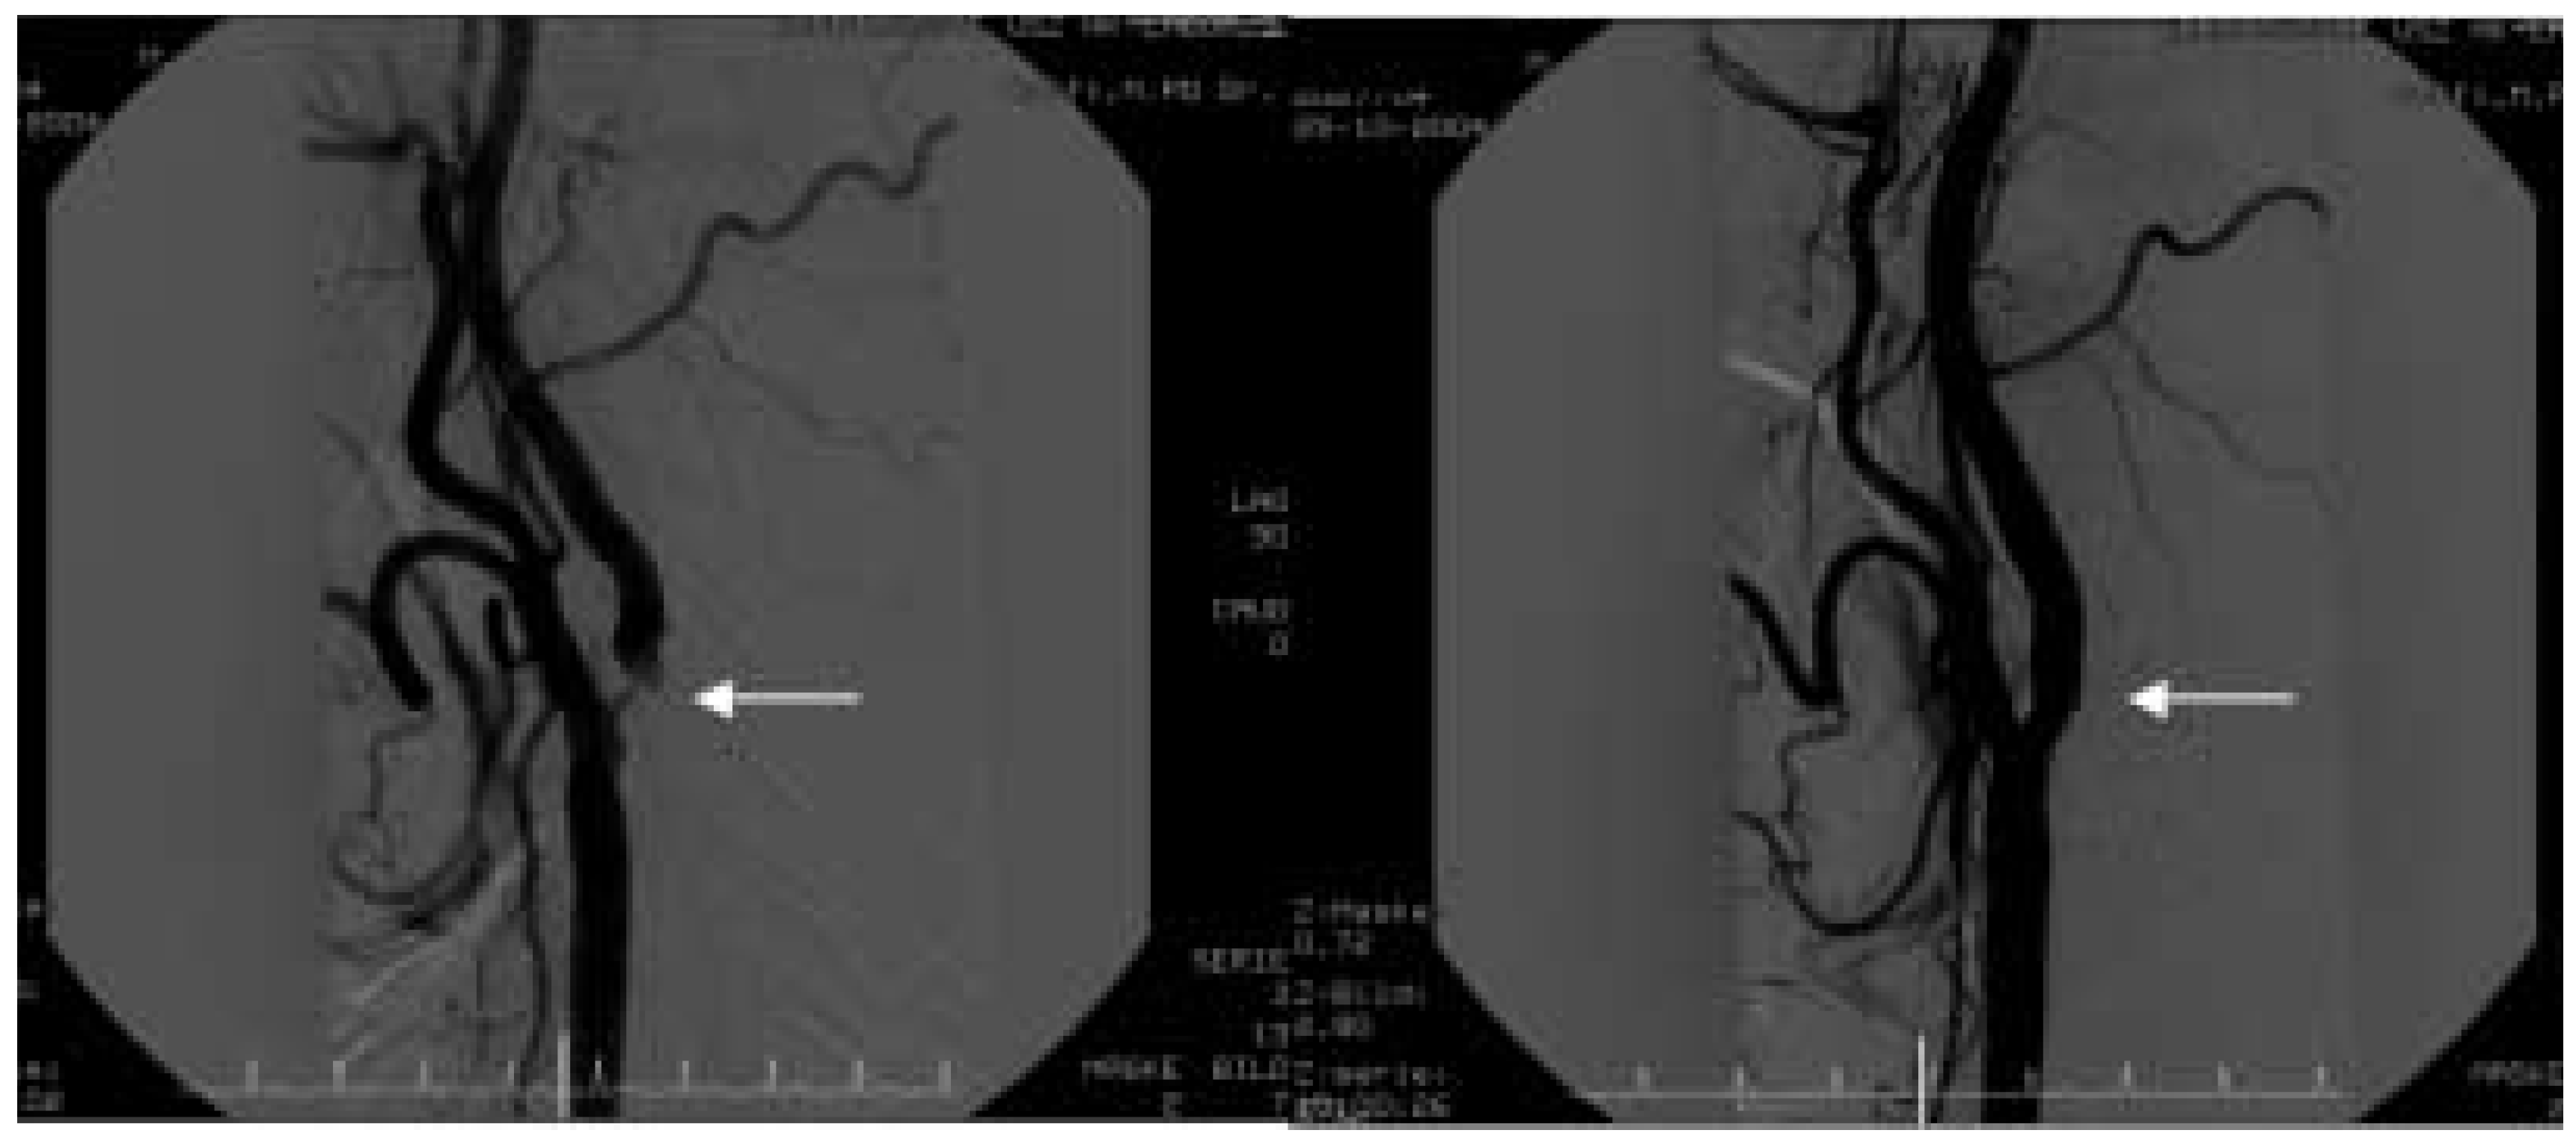

Man schätzt, dass bis 1999 ungefähr 3000 perkutane Eingriffe an den Karotiden weltweit durchgeführt wurden. Zunächst wurden nur Dilatationen mit Ballon-Kathetern durchgeführt, im Verlauf ersetzte die Stent-Einlage aufgrund der besseren Resultate, die reine Ballon-Angioplastie. Vom Jahr 2000 an nahm die Anzahl der perkutanen Karotis-Interventionen exponentiell zu. Man schätzt, dass 2003 lediglich in den USA ca. 15000 Karotis-Stenting-Eingriffe durchgeführt wurden (ungefähr 10% aller Endarterektomien). Die rasche Zunahme der Fallzahlen hat mehrere Erklärungen: die zunehmende Erfahrung der Interventionalisten, die optimierte plättchenhemmende Therapie (Aspirin und Clopidogrel) und die technischen Fortschritte im Materialwesen (Katheter, Ballone und insbesondere Embolieprotektionssysteme). Der Eingriff wird, ähnlich wie bei der Herzkatheteruntersuchung, durch einen femoralen arteriellen Zugang in Lokalanästhesie durchgeführt. Mittels Digitalsubstraktionsangiographie werden vor und nach dem Eingriff die Verhältnisse sowohl lokal (Abb. 1) als auch intrakraniell (Abb. 2) erfasst. Distale Embolieprotektionssysteme (Abb. 3, 4), welche die Inzidenz von neurologischen Ereignissen beim Karotis-Stenting signifikant reduziert haben [14, 15], sollten konsequent gebraucht werden. Der Patient wird postinterventionell neurologisch und hämodynamisch überwacht und meistens am nächsten Tag entlassen. Die nötigen prä- und postinterventionellen Massnahmen / Untersuchungen sind in Tabelle 1 zusammengefasst. Im Gegensatz zu den Koronareingriffen ist die Restenose nach Stenting der Karotis selten (4–7%) [16].

Abbildung 2. Intrakranielle Digital-Subtraktionsangiographie vor (links) und nach (rechts) Stenting der Carotis interna rechts. Zu beachten ist die Zunahme des Blutflusses.